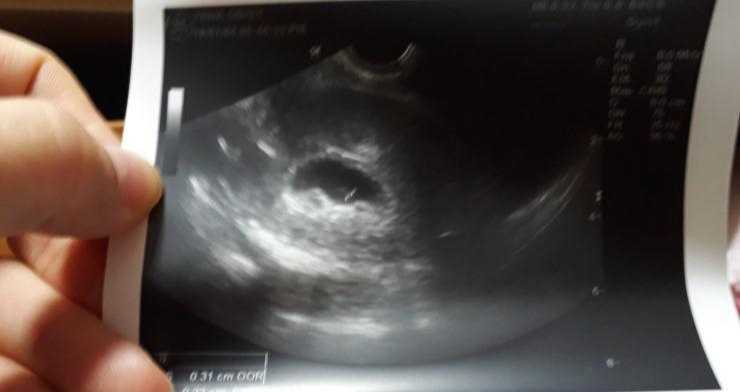

성인이 된 후 건강검진 때문에 산부인과를 찾은 적은 있어도 이런 일로 찾을 것이라고는 생각하지 못했다. 애엄마가 된 지금도 검사를 위해 다리를 벌리는 건 왠지 조금 부끄러운 마음이 든다. 초음파 검사 결과, 점처럼 작은 아기집만 있는 상태고 심장소리 등은 아직 들리지 않았다. 6주차라고 했다. 나나 남자친구나 얼떨떨한 건 마찬가지였다.

KakaoTalk_20180705_224148648.jpg 처음 아기집을 확인한 날. 말로 다 할 수 없는 복잡한 감정 가운데, 묘하게 설레는 마음도 있다는 점을 깨달았다.